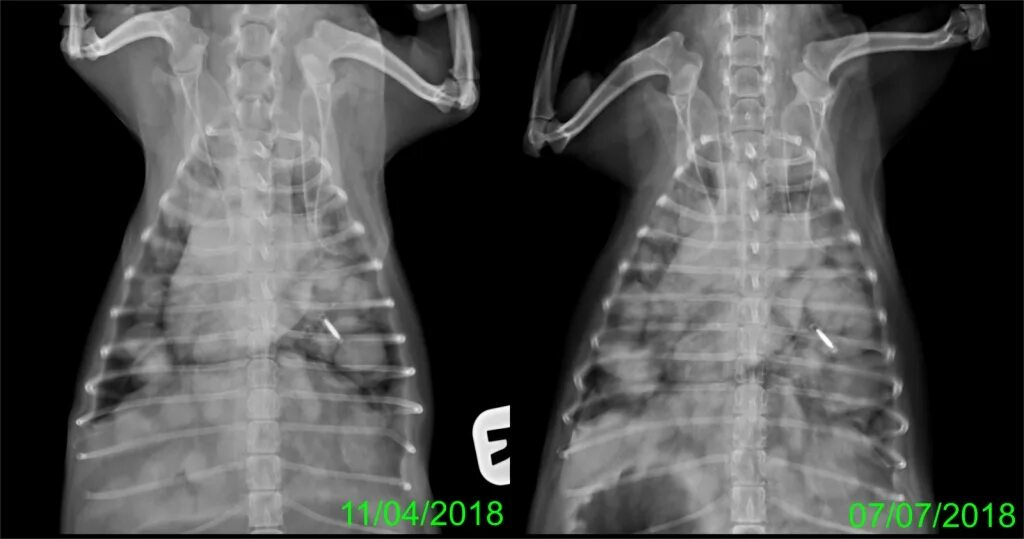

Вероятность метастаз